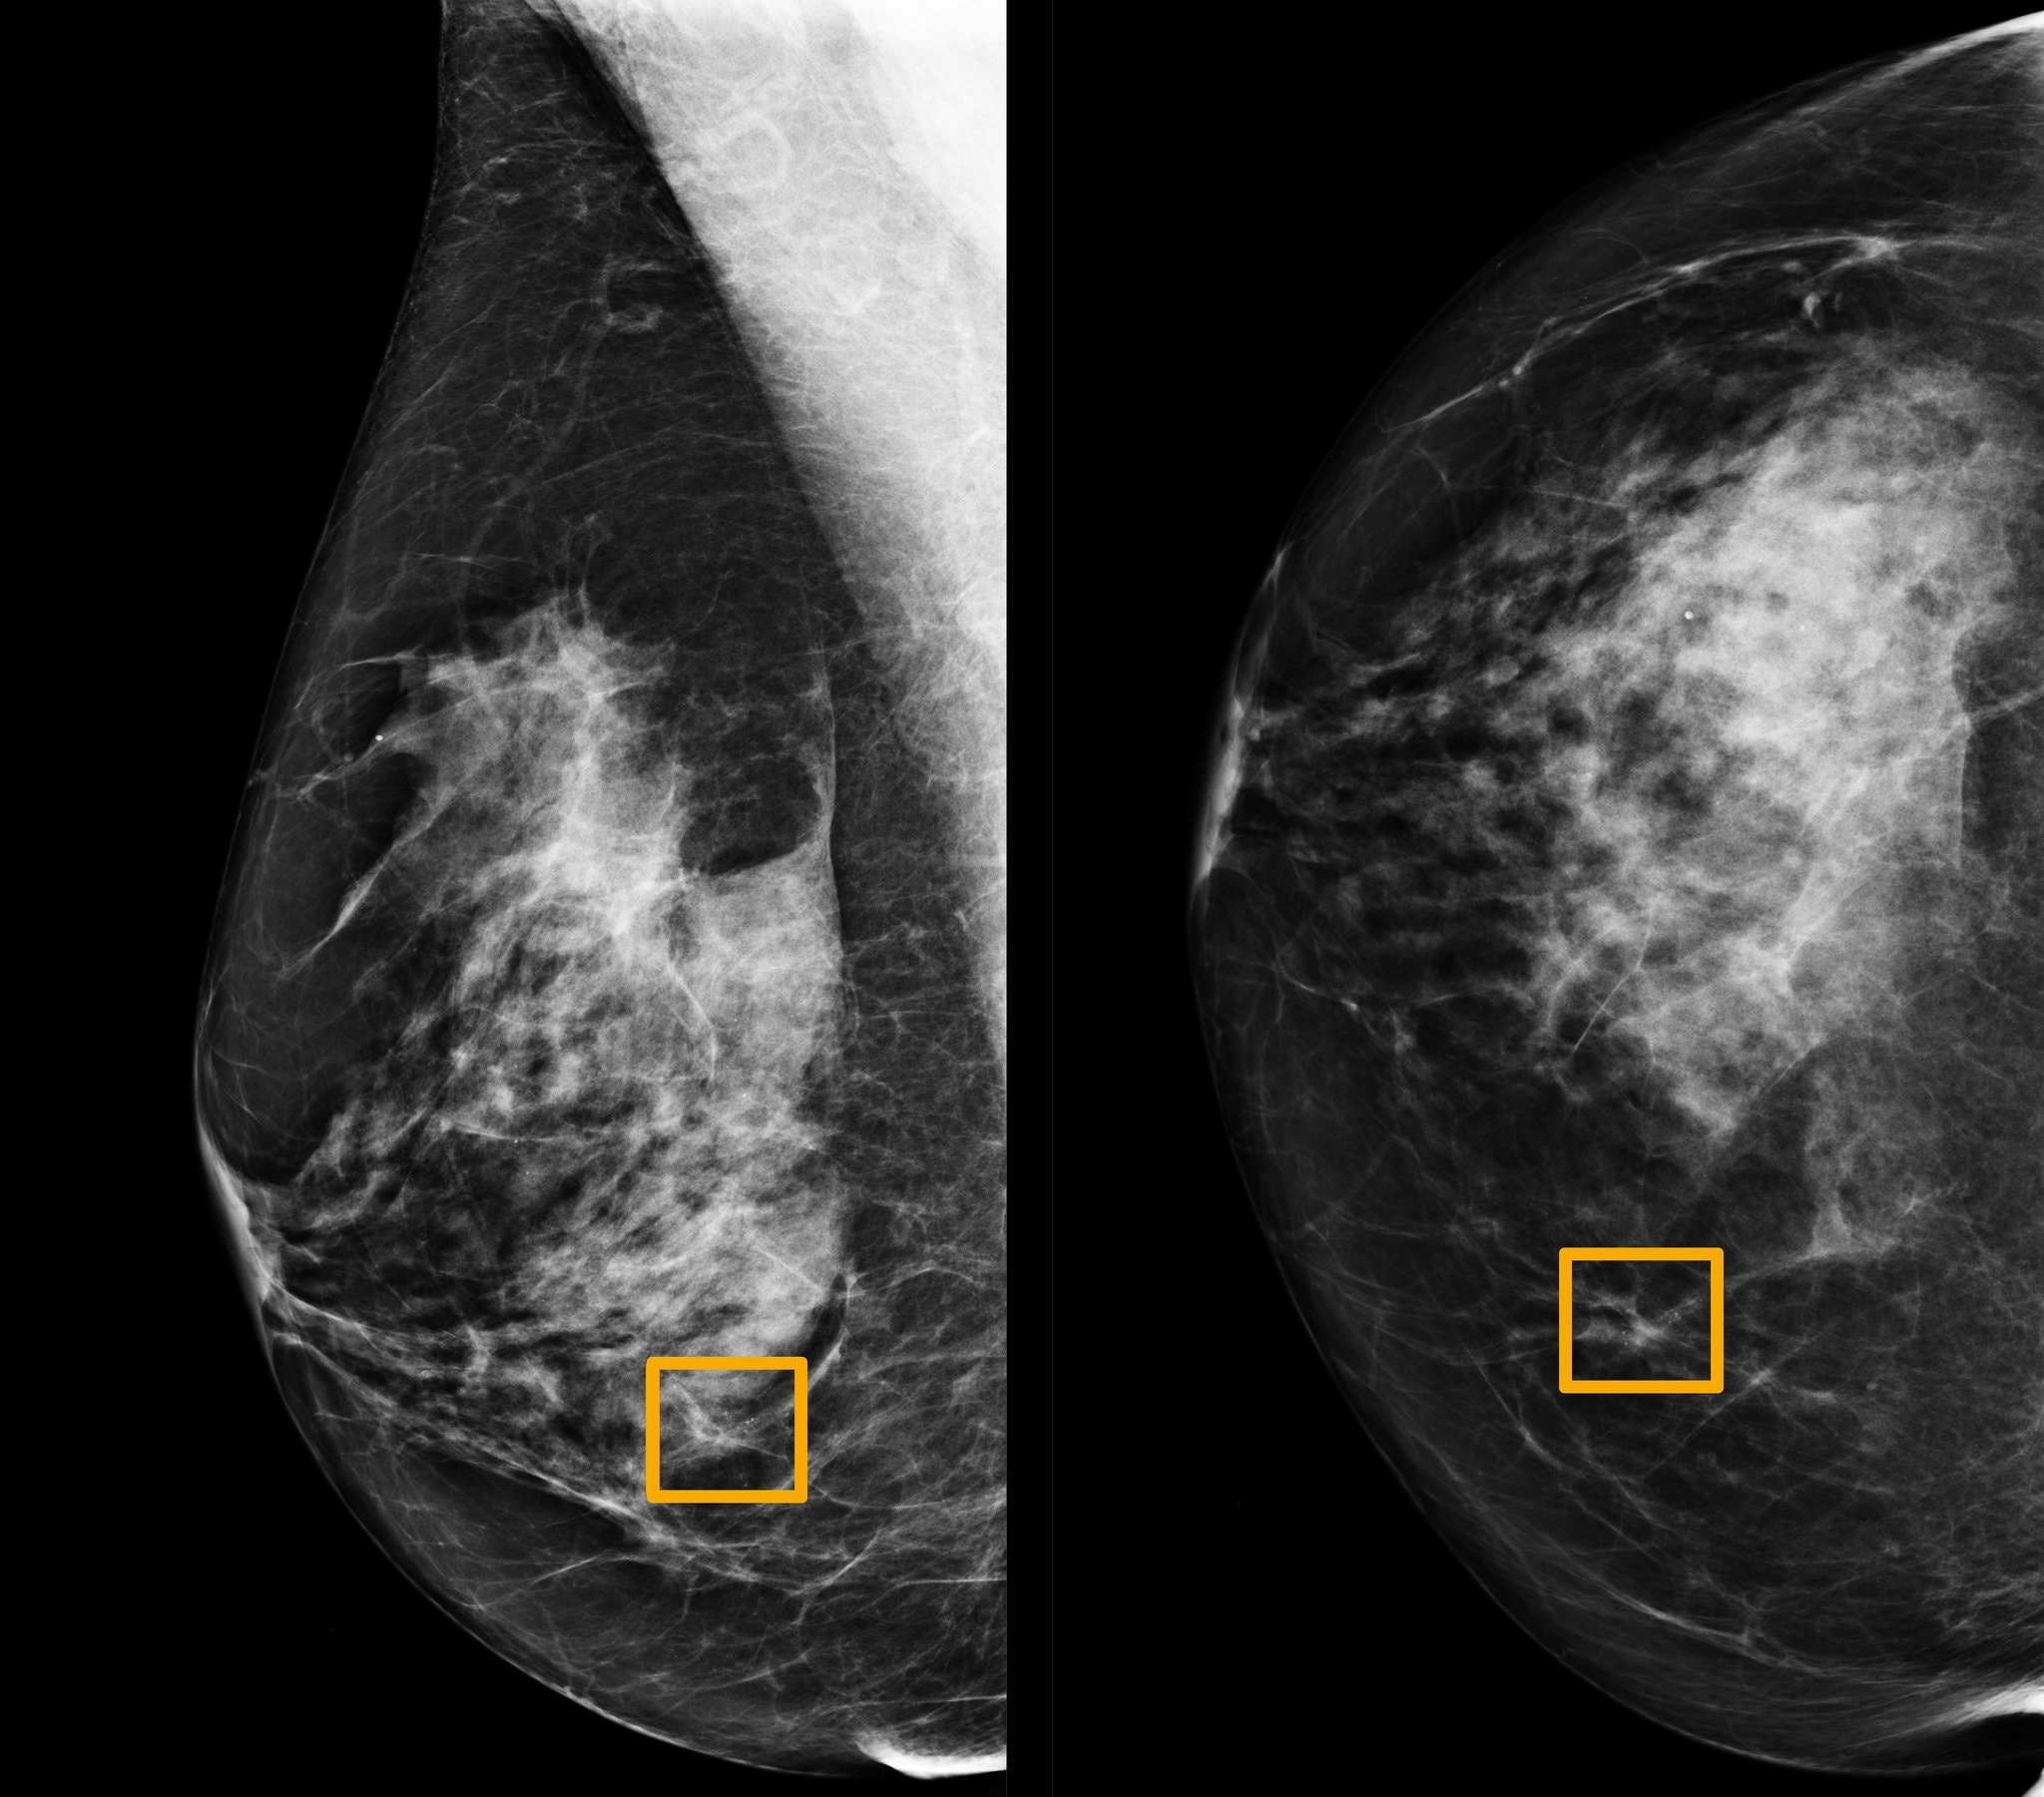

Sự phát triển của y học và công nghệ cho phép trí tuệ nhân tạo AI đọc quang tuyến vú, phát hiện ung thư. Ảnh: NY Times.